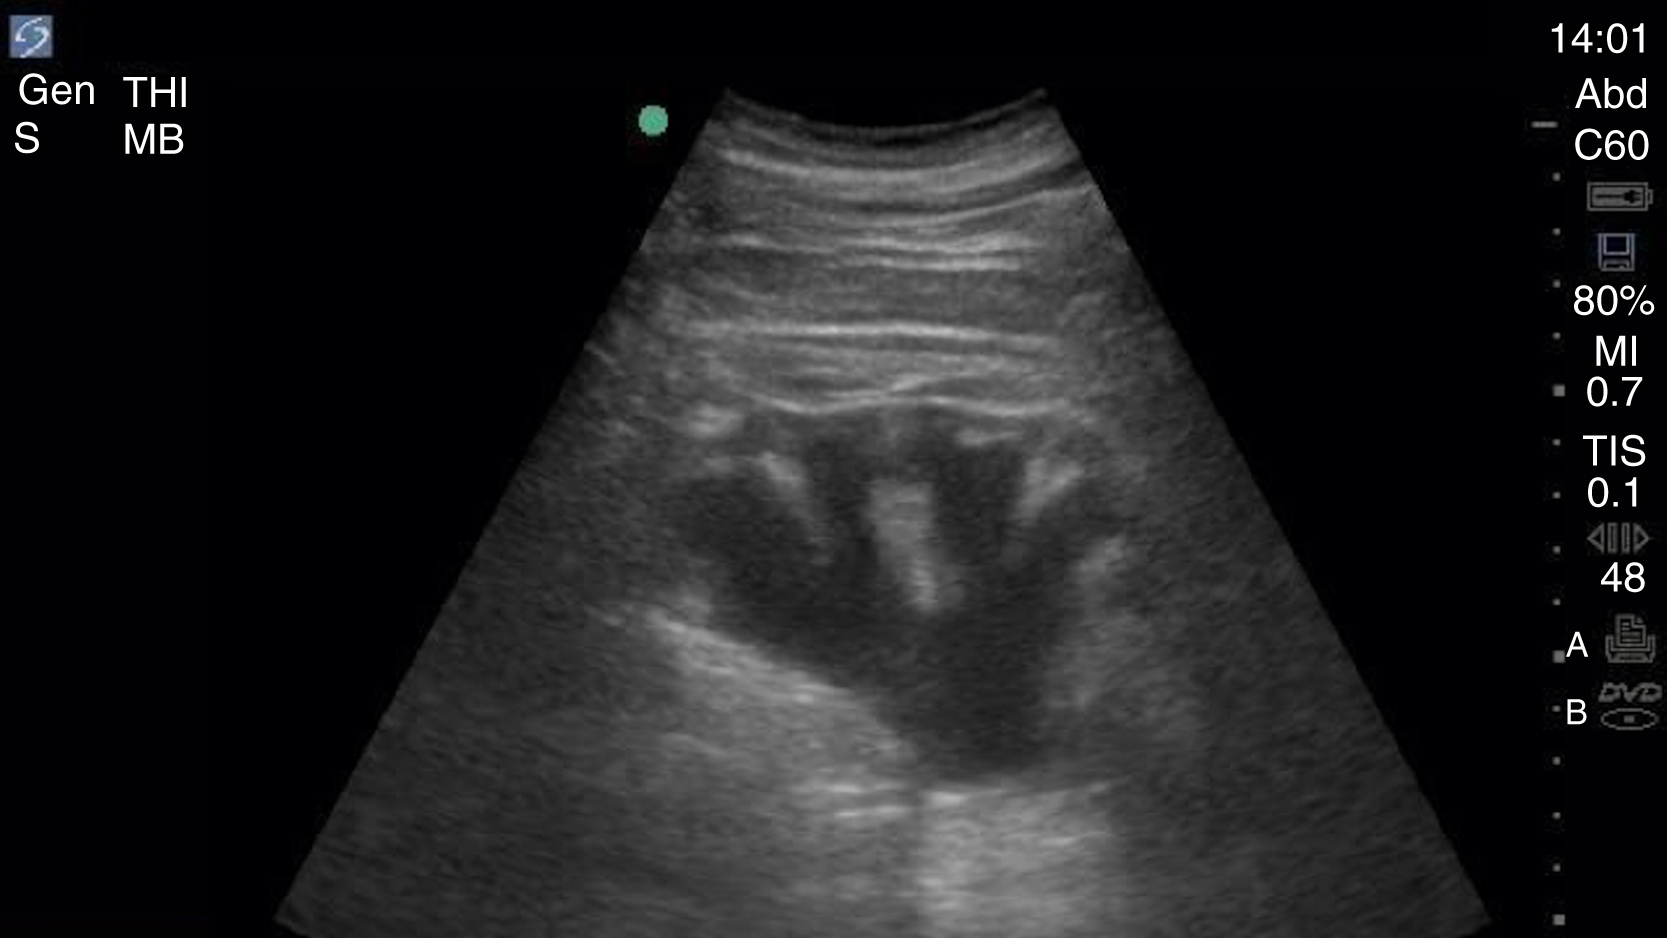

Image Acquisition

Cardiac US is performed through the transthoracic and transabdominal windows with the use of small curvilinear or phased array transducers. Typical views include the subcostal four-chamber view (subxiphoid), parasternal long-axis view ( Fig. e3.10 ; see Video e3.4 ), parasternal short-axis view, and apical four-chamber view. The subcostal four-chamber view, as in the FAST, is ideal for assessment of pericardial effusion and useful during cardiac arrest because it does not interfere with chest compressions. The long-axis subcostal view highlights the inferior vena cava (IVC) and can indicate volume status. The parasternal views are excellent windows for LV assessment. The apical four-chamber view is ideal for comparison of RV and LV sizes and function. Several US protocols have been developed to evaluate undifferentiated hypotension and can be used to narrow the differential diagnosis.

Fig. e3.10

Normal parasternal long-axis view of the heart.